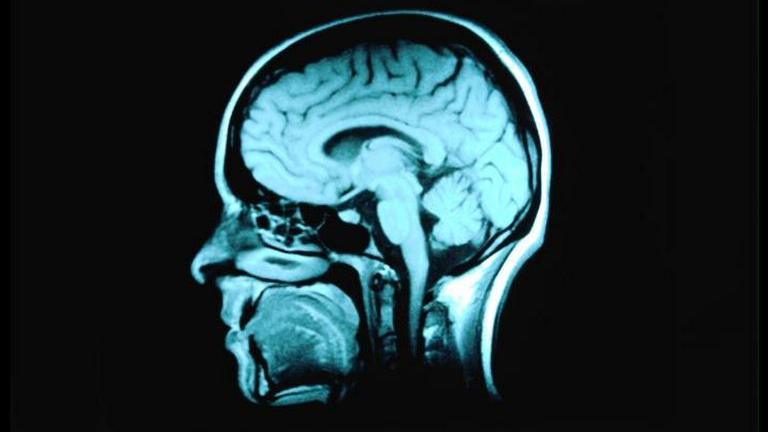

Magnetic resonance imaging, which generates 3D internal images of the body using strong magnetic fields and radio waves, was developed at the University of Nottingham by a team led by the late Sir Peter Mansfield in the 1970s.

The new machine will be able to see internal organs and processes in far greater detail, which scientists hope will help transform understanding of neurodegenerative diseases such as Alzheimer's, Parkinson's and Huntington's and neurodevelopmental disorders including autism and schizophrenia.

Even today, most clinical MRI machines typically operate at magnetic field strengths of 1.5T and 3T. The higher the Tesla, the greater the magnetic field and the higher resolution images and detailed information that can be produced.

A centre in Paris started using a 11.7T machine last year, and it has already led to some of the most detailed images so far of the human brain.